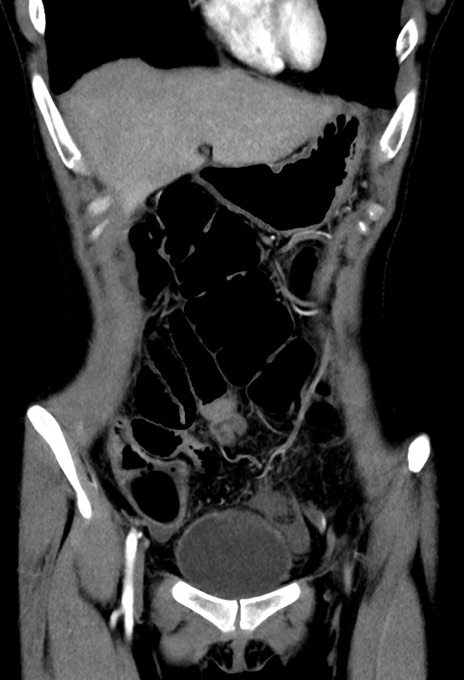

症例17(冠状断像)

【症例】20歳代女性

【主訴】嘔吐、下腹部痛

【現病歴】昨日夕食後に嘔吐し下腹部痛が出現。本日になっても嘔吐持続し改善しないため来院。

【身体所見】意識清明、BT 37.2℃、BP 108/67mmHg、腹部:平坦、やや硬、下腹部正中から右にかけて圧痛あり、反跳痛軽度あり、tapping pain(+)。

【データ】WBC 13600、CRP 14.94